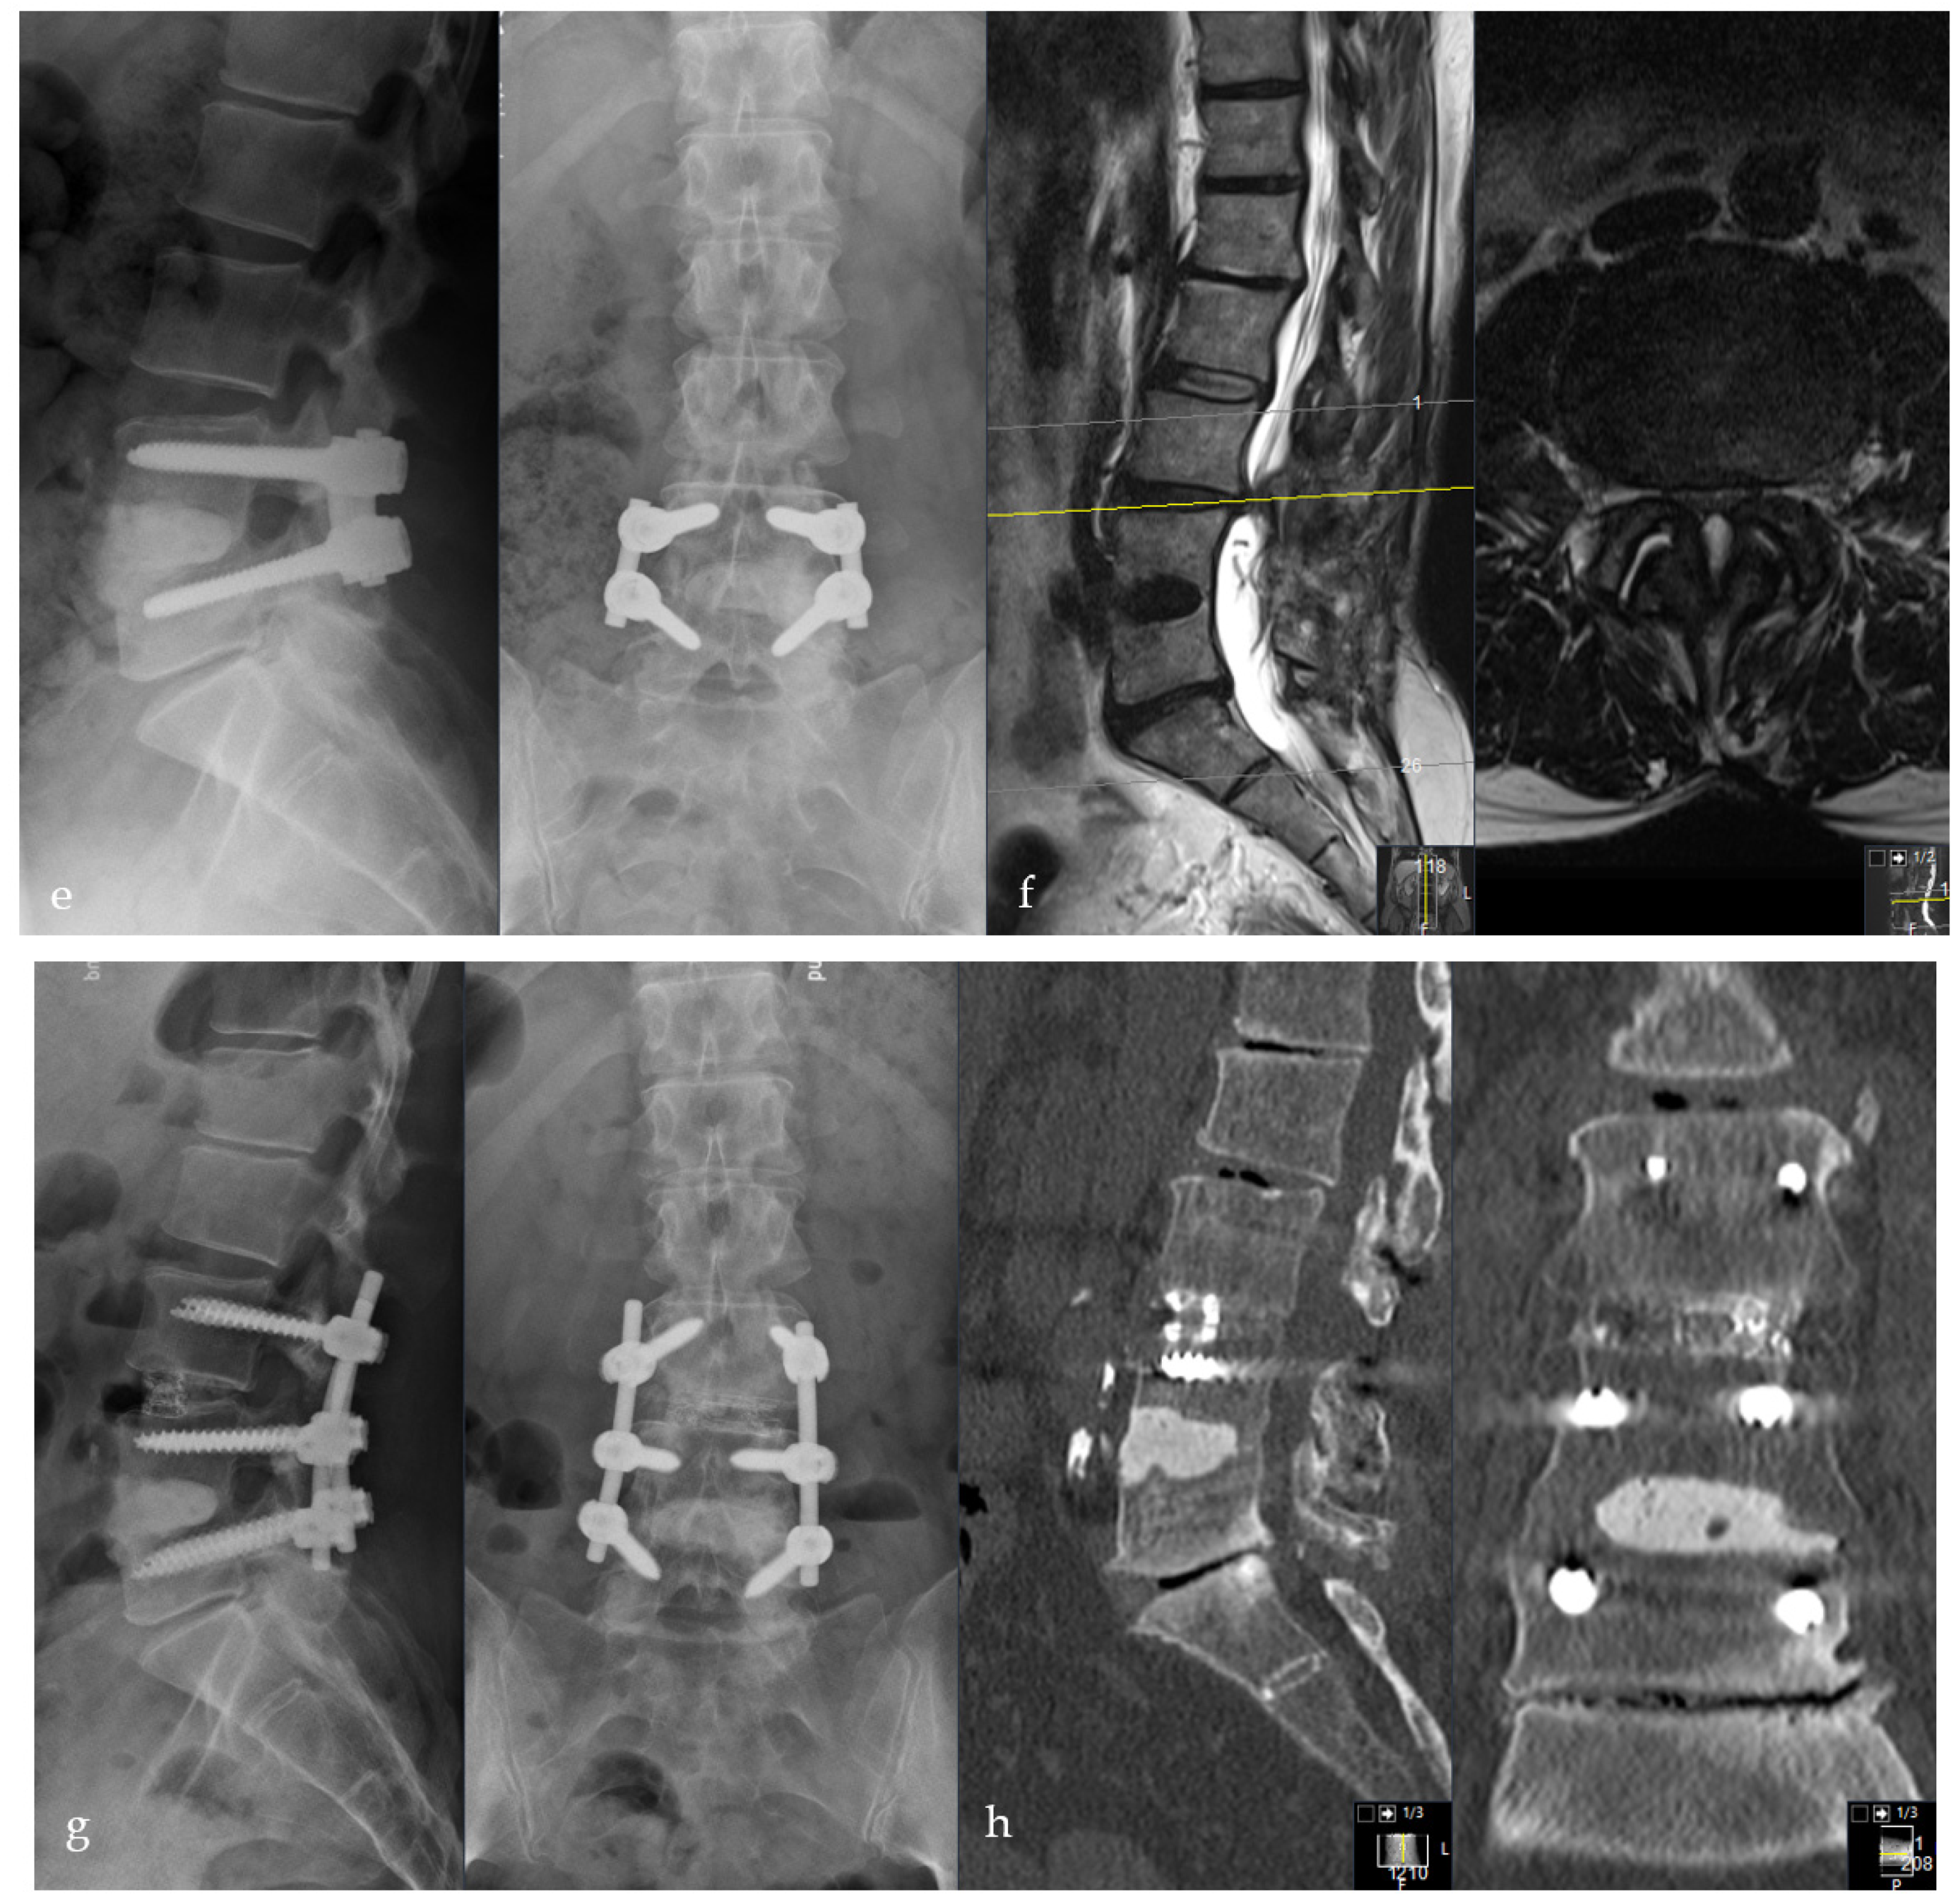

2.2. Surgical Procedure